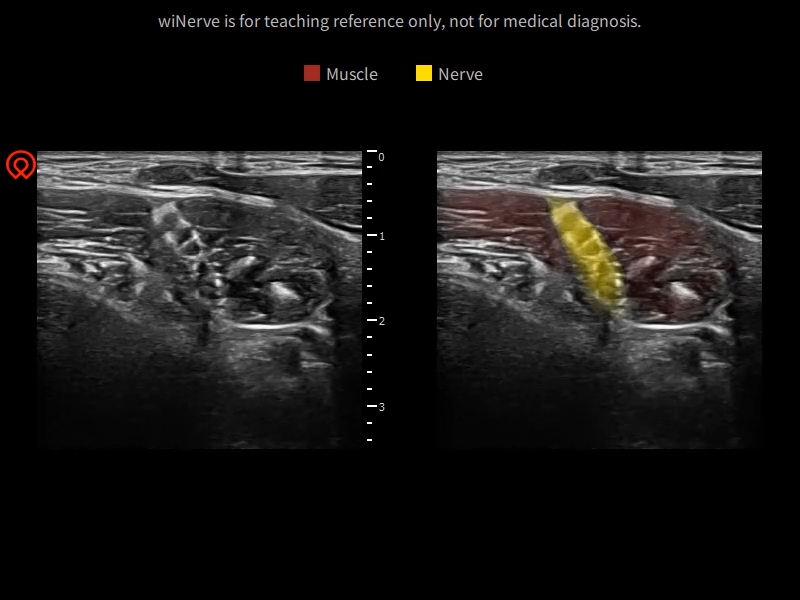

wiNerve - AI intelligente neuronale Erkennung

Echtzeit-Identifikation

Cloud-L?sung

Unterstützt mehrere Nerven

Online Unterstützung